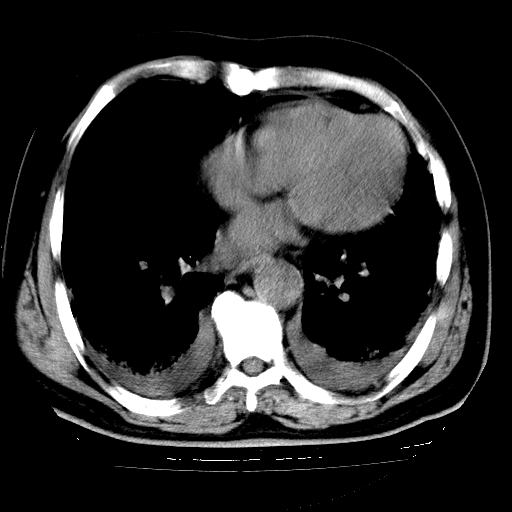

男,68岁,咳嗽、胸闷、发烧三天,查体:双肺散在湿罗音。

1.双肺间质纤维化并感染;

4.肺原性心脏病;

5.双侧胸腔少量积液;双侧胸膜增厚。

慢支合并感染.间质纤维化,心衰双侧少量胸腔积液

两肺广泛条索状、网格状、蜂窝状改变。肺间质纤维化,肺心病,双侧胸腔积液